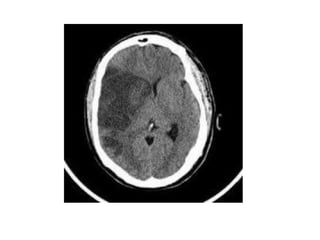

CT SCAN OF BRAIN

Ct scan lecture